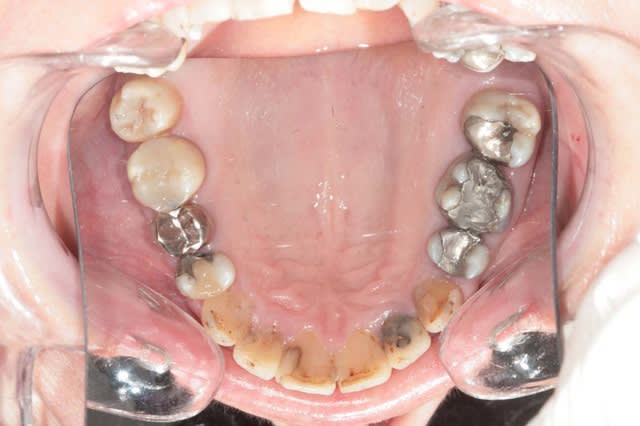

Voila la suite pour le maxillaire, le wax est fait sur arti en fonction de l'OIM obtenue après ortho. seule la 27 restera intacte.

Préparation des molaires pour permettre des RTE sous digue à travers les provisoires, retrait des anciennes couronnes et ancrages sur les 12, 15 et 25 endo satisfaisantes (couronnes ayant plus de 30 ans pour certaines!!!.

Tailles parallèles pour zircone 13 à 23 seront solidarisées pour éviter une migration post ortho.

Gingivectomie légère à la fraise à biseau pour harmoniser les collets, mais l'ortho a permis d'énormément faciliter ce travail.